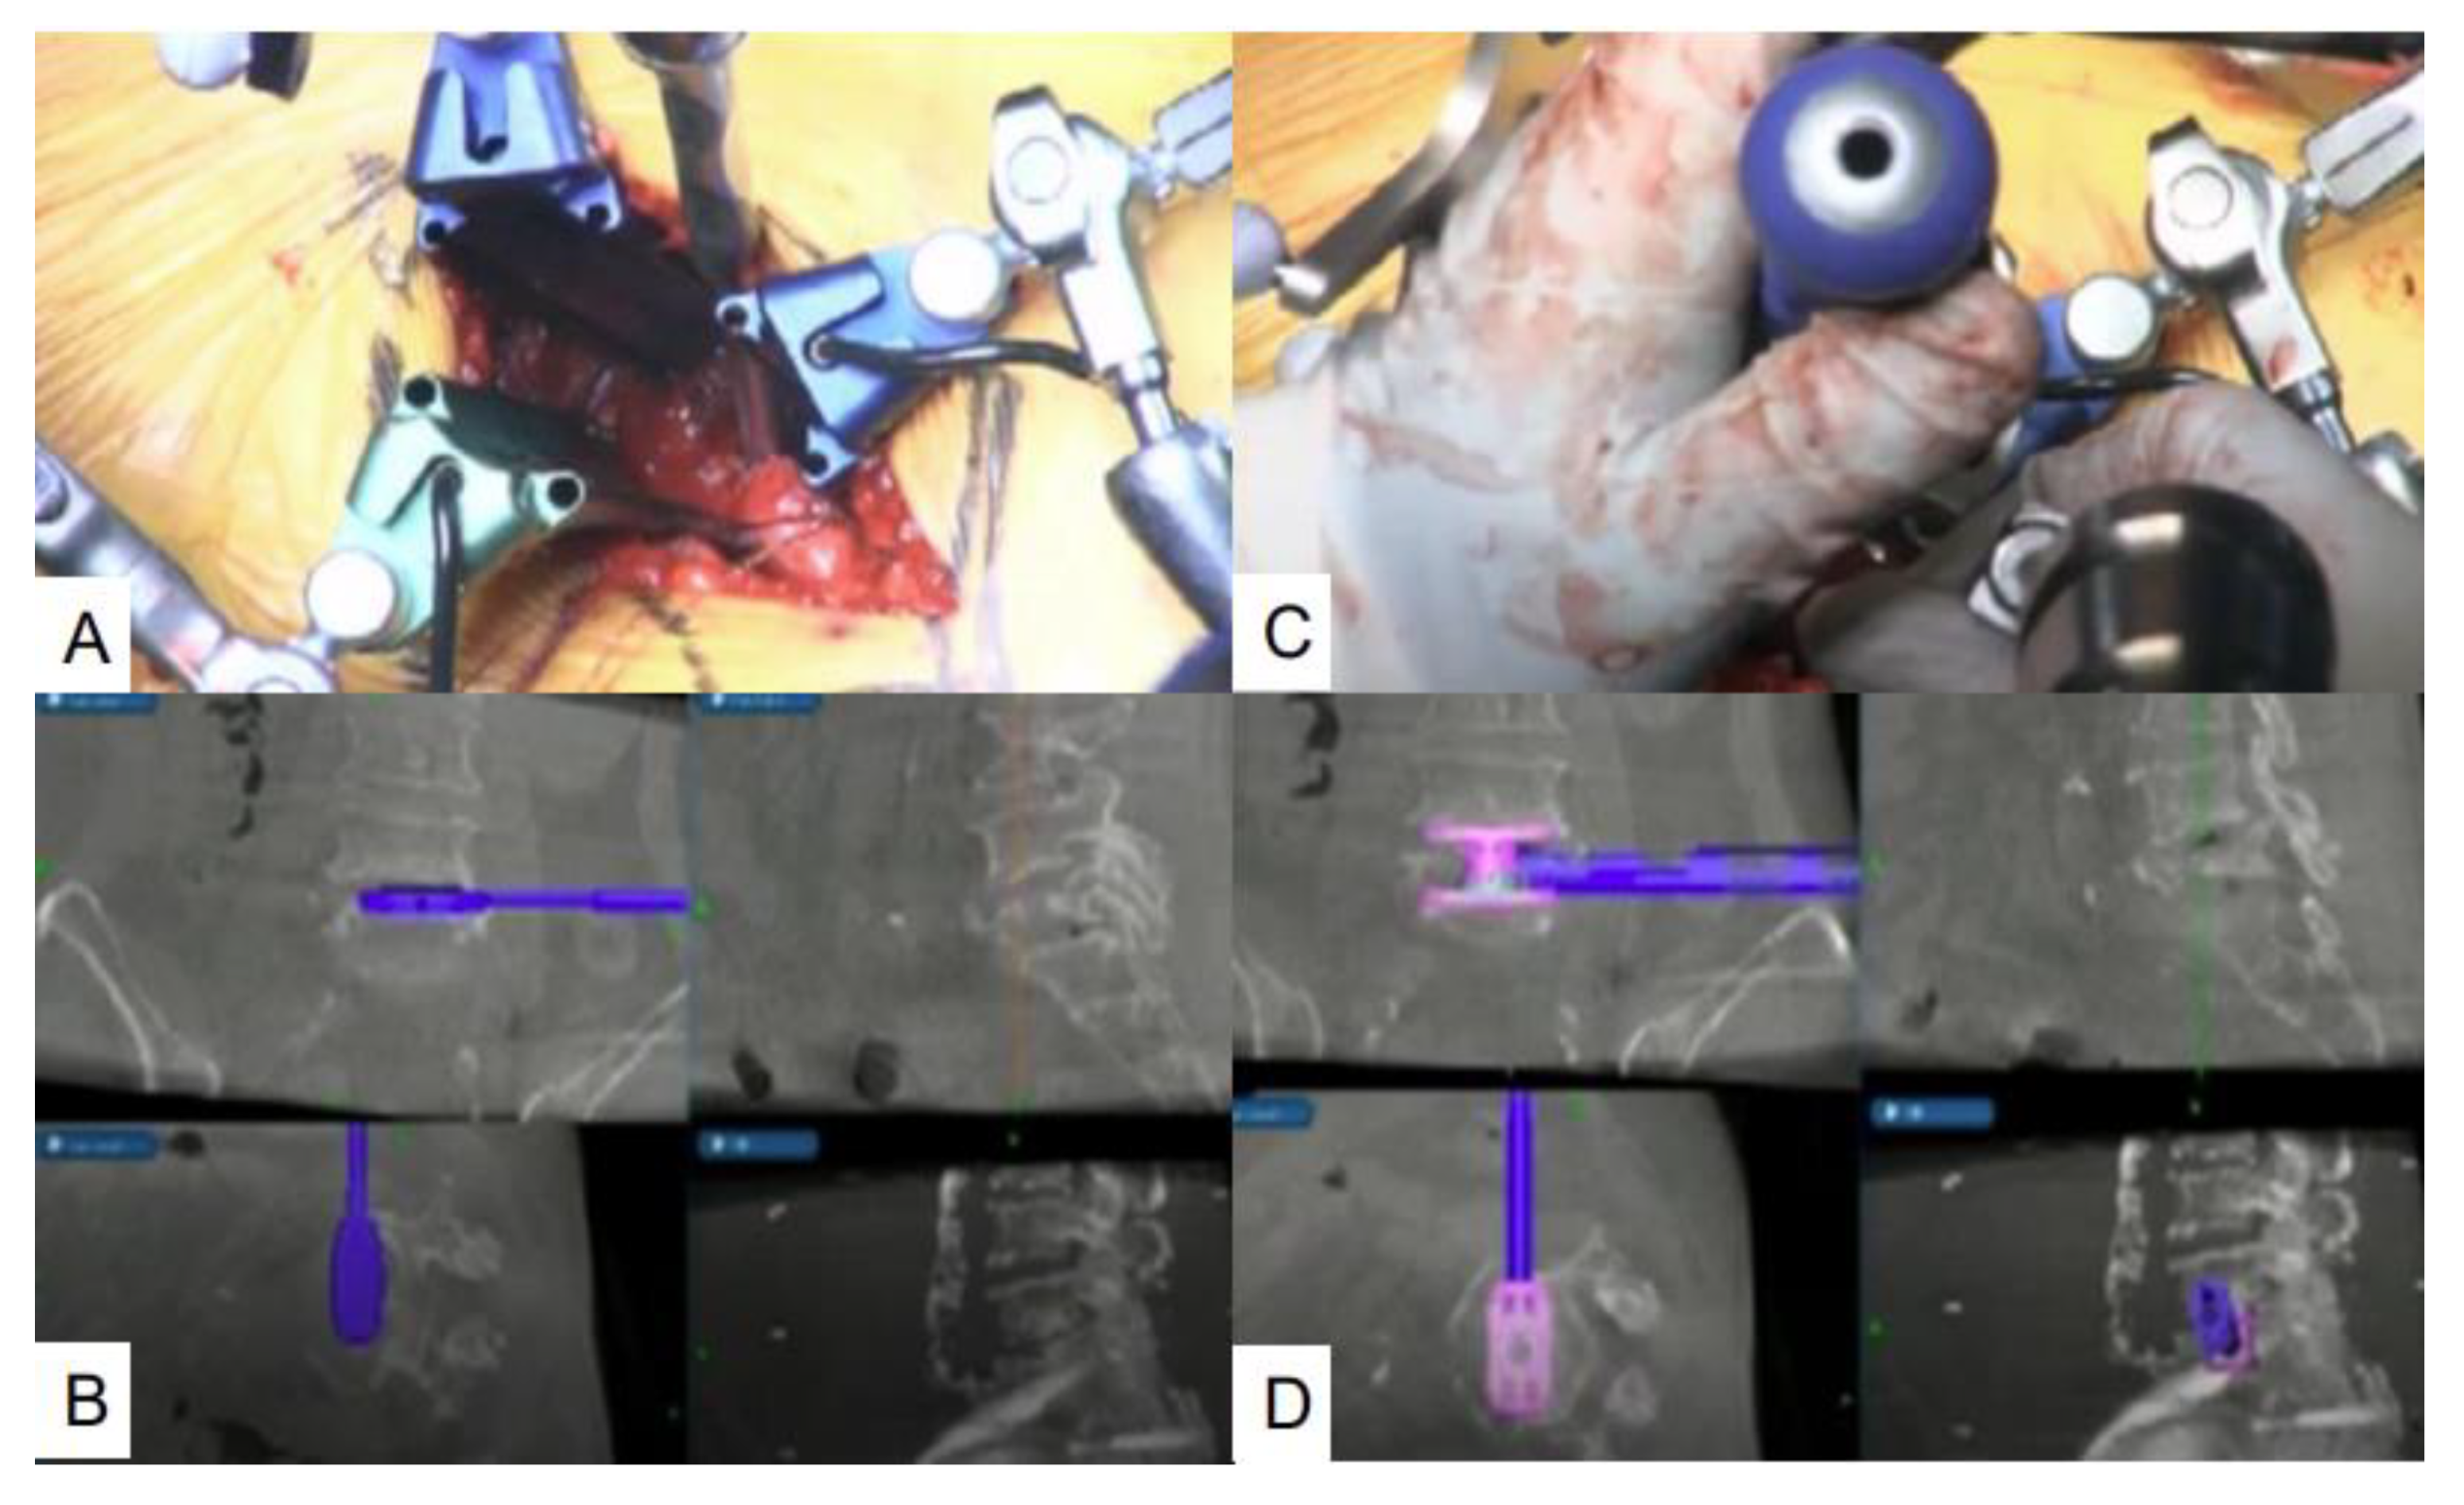

3. Operative Procedure

3.1. Mini-Extraperitoneal Approach

3.2. Corpectomy with Navigation

3.3. Navigated Expandable Vertebral Cage